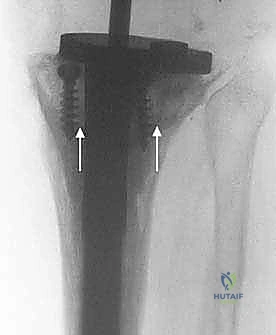

تُستخدم هذه التقنية في حالات الفقدان العظمي البسيط جداً (عيوب أقل من 5 ملم). يتم ملء الفجوة الصغيرة بالإسمنت العظمي الطبي. وفي بعض الحالات، يتم إدخال براغي معدنية في العظم ثم تغطيتها بالإسمنت لزيادة قوة التحمل وتوزيع الضغط.

2. الدعامات المعدنية (Metal Augments / Blocks)

عندما يكون الفقدان العظمي متوسطاً (من 5 إلى 15 ملم) ومحصوراً في جانب واحد أو جانبين من قصبة الساق، يتم استخدام كتل أو أسافين معدنية (مصنوعة من التيتانيوم أو الكروم كوبالت). يتم تثبيت هذه الدعامات بمسامير أو إسمنت في الجزء السفلي من صينية المفصل الصناعي لتعويض الارتفاع المفقود واستعادة الاستواء الميكانيكي للركبة.

5. السيقان الممتدة (Intramedullary Stems)

في جميع حالات المراجعة تقريباً، لا يمكن الاعتماد فقط على الجزء العلوي من قصبة الساق للتثبيت بسبب ضعف العظم. لذلك، يتم استخدام مفاصل ذات "سيقان" معدنية طويلة تمتد داخل القناة النخاعية لعظم قصبة الساق (Diaphysis). تقوم هذه السيقان بنقل الضغط والوزن من المنطقة الضعيفة في الأعلى إلى العظم القوي في الأسفل، مما يحمي المنطقة المعاد بناؤها ويضمن استقرار المفصل.